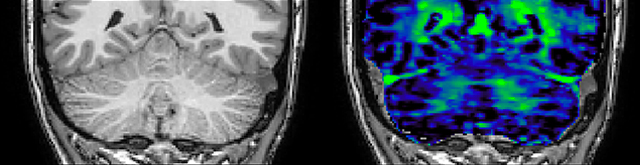

At UBC, a lot of the MS-related work focuses on myelin imaging. “We're born with very little myelin and that increases as the brain grows, which is important for nerve signal propagation. Multiple sclerosis on the other hand, degenerates the myelin with the opposite effect. So, myelin has a really important role in brain function, and having a tool that measures myelin can be extremely useful, we feel,” says Dr. MacKay.

Myelin water imaging (MWI) is a breakthrough technique that was pioneered at UBC for measuring myelin content in the brain, in vivo. “Because the T2 time of water in myelin is much shorter than the T2 of water in the intraand extracellular spaces, we can separate out the myelin water signal.”

The techniques for measuring myelin have changed a lot over the years. “Since we are using the Elition, our myelin water images are much better. We're now acquiring 1 x 2 x 5 mm voxels and displaying at 1 x 1 x 2.5 mm. For a whole brain we can now measure the fraction of water in the myelin component in only about five or six minutes,” Dr. MacKay says.

of limiting MWI to the brain, even without the cerebellum, we can now spend about the same amount of time and scan the whole brain and the cervical spinal cord, which is a huge boost for us.” Dr. Rauscher says, “For MWI we perform 3D T2 with 32 or more echoes. This used to take a long time, but with Compressed SENSE we can decrease this to ten minutes for the whole head. Because of the large field of view (FOV) on the readout direction, we even get information from the brainstem, which we previously missed when we were using the GRASE approach. Having the whole head scan is nice because it has spatial resolution, orientation and FOV that are comparable to the standard 3D clinical MS scans, including the FLAIR and 3D T2, and a 3D T1 for brain volume.”

T1 - Weighted, Myelin Water Fraction Superimposed

Spinal cord coverage

Smaller, more isotropic voxels

Excellent detail in quantitative maps

Images courtesy of Adam Dvorak, Department of Physics and Astronomy, University of British Columbia